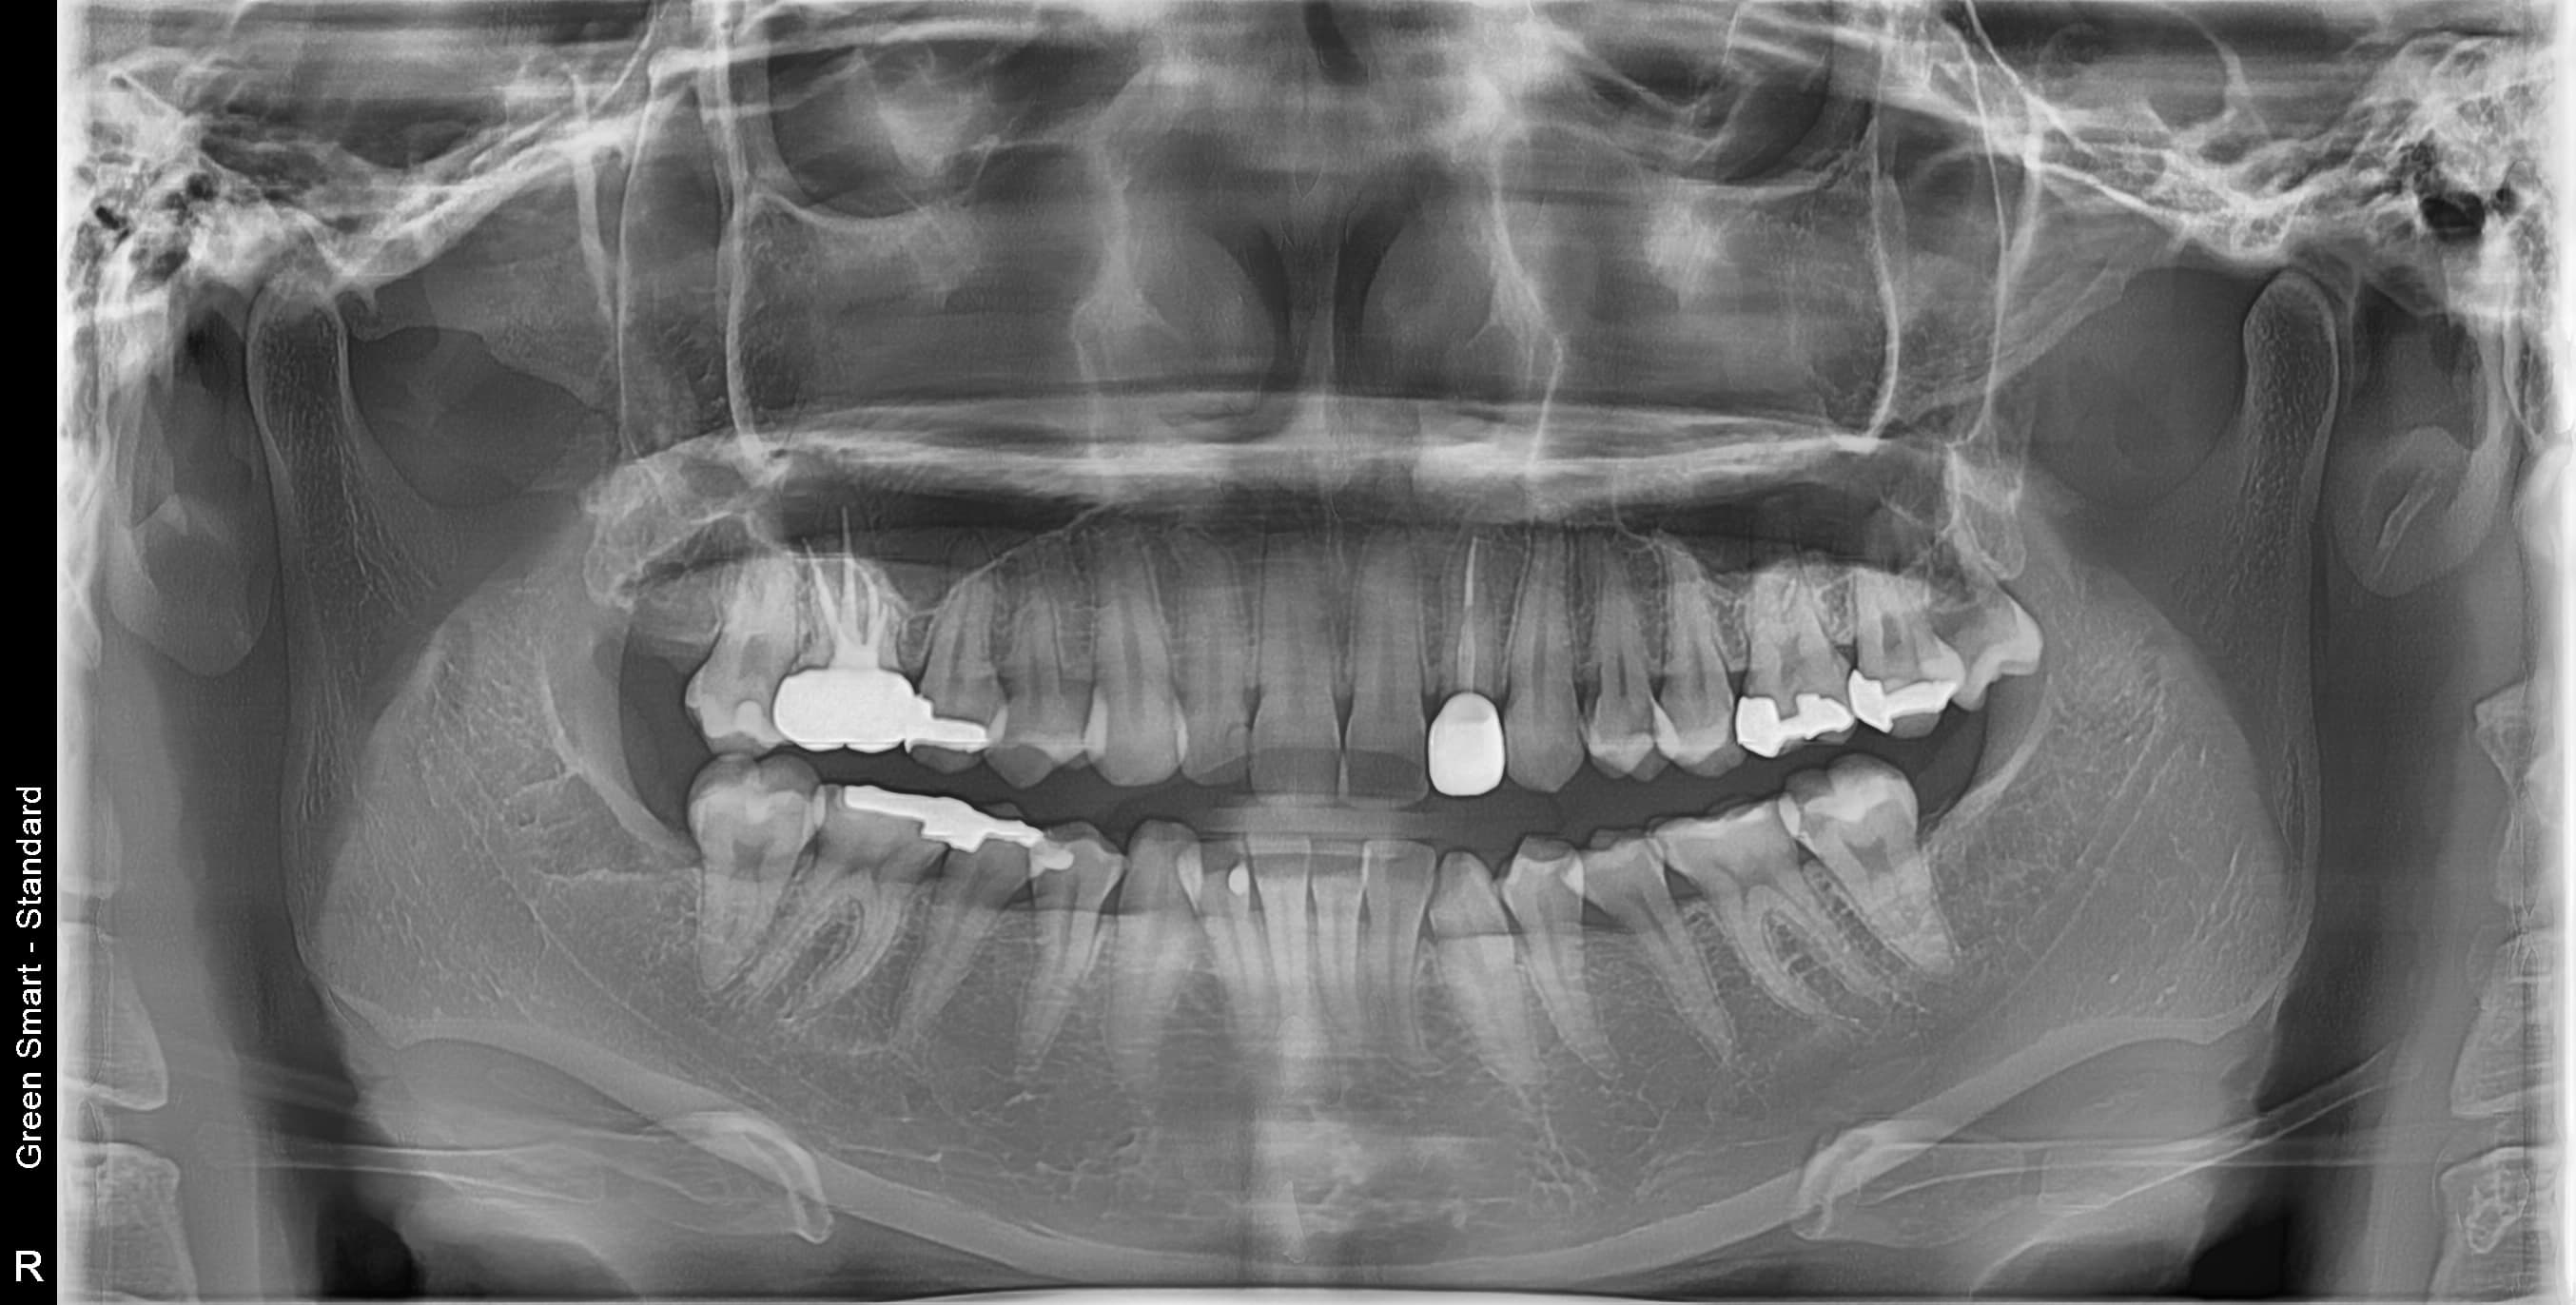

대학병원급 난이도 발치

일반 치과에서

"큰 병원 가보세요" 들어보셨나요?

복잡한 매복 사랑니 — 잇몸 속 깊이 묻혀있어도 OK

신경 근접 사랑니 — 신경 손상 걱정 없는 안전한 발치

수평 매복 사랑니 — 옆으로 누워있는 어려운 케이스도 가능

조선대 치과병원 외래교수 역임 원장이

직접 안전하게 해결합니다

난이도 높은 사랑니도 뽑을 수 있나요?

네, 가능합니다. 고덕퍼스트치과는 풍부한 발치 경험과 대학병원급 난이도 발치가 가능한 시스템을 갖추고 있습니다. 수평매복, 완전매복 등 일반 치과에서 큰 병원을 권유하는 어려운 케이스도 3D CT 정밀 진단으로 안전하게 발치합니다.